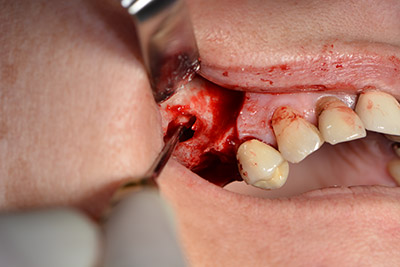

Le vie indicate di seguito sono realizzate con una perforazione a velocità ridotta, pari a 300 rpm. In questa fase Implantmed dimostra la sua grande affidabilità. È possibile predefinire il protocollo chirurgico: per selezionare le varie posizioni, basta premere la lettera “P” con il controllo a pedale (da fig. 10 a 11).

Il passaggio successivo consiste nel posizionamento dell'impianto, che nel nostro studio prevede una potenza pari a 32 Ncm (fig. 12).